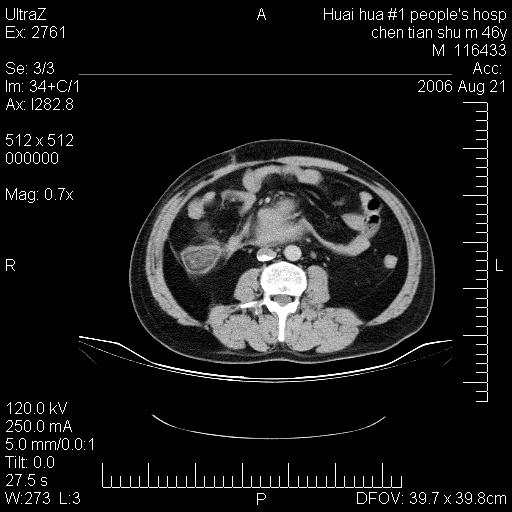

患者,男,46y。腹痛2月,消瘦。

十二指肠水平段占位,考虑间质瘤或平滑肌瘤。

肿块较大,腹膜后占位,境界欠清,周边脂肪密度较高呈条状影,有没有脂肪肉瘤可能,

缺少完整的三期图像。考虑肠系膜脂膜炎mp(肿块型)。

鉴别:间质瘤(这么大而无囊变不可思议)、平滑肌瘤/肉瘤、淋巴瘤、类癌,脂肪类肿瘤、转移瘤等。

十二指肠水平段占位,考虑间质瘤。

首先考虑小肠间质瘤。

十二指肠水平段软组织密度占位,考虑间质瘤可能性大。

腹膜后占位,境界欠清,考虑来源于十二指肠病变,间质瘤或平滑肌肉瘤可能性大。建议活检。

手术病理结果:原发性小肠恶性淋巴瘤(primary gastrointestinal lymphoma,pgil)是原发于胃肠的淋巴网织系统的恶性肿瘤,在结外淋巴瘤中居第一位,该病少见,临床无特异性,诊断困难,术前主要依靠影像学诊断。胃肠道本身具有较丰富的淋巴组织,因而胃肠原发性淋巴瘤是结外淋巴瘤最常见的部位,文献报道约占胃肠道恶性肿瘤的1%~4%,其中胃约占50%~70%,小肠约占35%~70%,结肠约占4%~6%。影像检查在pgil的诊断及分期中有重要的作用,ct是很有价值的检查方法。

胃肠淋巴瘤病理特点:胃肠道原发性淋巴瘤起源于胃肠壁固有层和黏膜下层的淋巴组织即胃肠粘膜相关淋巴组织(malt),多为粘膜相关淋巴瘤。病理上通常为非霍奇金淋巴瘤,且决大多数来源于b淋巴细胞,很少见于霍奇金淋巴瘤。胃肠原发淋巴瘤比胃肠道癌的发病率要低的多,最常见于胃,其病因可能跟幽门螺杆菌感染有关。幽门螺杆菌能引起胃粘膜损害,引起炎性及免疫反应,淋巴细胞聚集并形成滤泡,可影响胃的正常生理功能,导致胃淋巴瘤的发生。单纯性小肠淋巴瘤是常见好发于回盲末端,受累的肠段较长,可单发、多发,甚至累及整个小肠。原发性大肠淋巴瘤罕见,以直肠和盲肠最多见。病变大体观可表现为胃肠腔内外的肿块,也可表现为从黏膜下到浆膜面肠壁的纵向浸润,并且常常伴有肠系膜淋巴结肿大。任何情况下,肿瘤几乎总是导致一定程度的肠壁增厚,可对称或不对称,病变与正常组织间常无明确分界,肠腔可狭窄、正常或动脉瘤样扩张,后者主要是肿瘤在肠壁内浸润,破坏肠壁内植物神经丛所致。以上改变成为ct检测病变的病理基础。

肠道淋巴瘤的ct表现分为4类

1) 壁内浸润型, (2)多发结节型, (3)肠系膜受累伴腔外肿块型(本型就是),(4)肿块型。